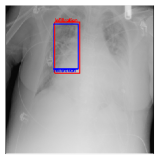

IV-D Investigation of the generated heatmap

By using the training result of the Adaptive DBN, the heatmap images were generated in addition to detection of B-Box. The heatmaps in Fig. 10 to Fig. 14 show the detection result of B-Box and the generated heatmap for some images. The red and blue rectangles in the image are given B-Box and detected B-Box, respectively. A heatmap is represented by the continuous value of range [0,255]0255[0,255], where the color map is jet color array (red means high value, while blue means small value). The diseases for detected B-Boxes in Fig. 10 to Fig. 14 were as follows; Infiltration (Fig. 10), Mass (Fig. 10), Nodule (Fig. 10), Mass and Pneumothorax (Fig. 10), Atelectasis (Fig. 14), Infiltration (Fig. 14), Atelectasis (Fig. 14), Atelectasis (Fig. 14).

Overall, the red area of the generated heatmap included in both the given B-Box and detected B-Box. On the other hand, the blue or yellow areas didn’t include in these B-Boxes. This tendency was seen in not only large diseases (e.g. Cardiomegaly or Infiltration) such as Fig. 10, but also small diseases (e.g. Mass or Nodule) such as Fig. 10. We consider that the experimental results caused by the discrete heatmap with binary output of final RBM layer instead of continuous heatmap. As a result, the red regions represents localization with strong relation to diseases and blue regions represents localization with weak relation. The generated heatmap shows the portion with strong relation more clearly.

In Fig. 14, the detected B-Box was located at a little upper than the given B-Box. The red area of the heatmap was also at upper position. The detected B-Box is slightly larger than the given B-Box. The detected B-Boxes are almost same as the given B-Boxes except the different size. For better detection capability, the feature of the generated heatmap will be investigated with the medical specialists.